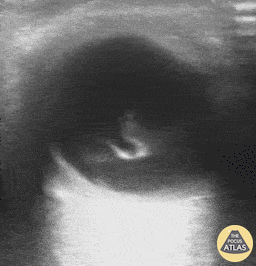

Orbital - Vitreous Hemorrhage

A 71-year-old male with a history of hypertension and diabetes presented to the ED reporting gradual vision loss in his right eye over a 3-day period. Physical exam was notable for a 3 mm and nonreactive pupil with ipsilateral visual acuity reduced to patient only being able to detect movement. POCUS revealed swirling echodensity within the right eye, most appreciable with extraocular muscle movements. Ophthalmology subsequently confirmed our suspected diagnosis of vitreous hemorrhage. Richard Cunningham, MD @HappyDays_EM Maricopa Medical Center